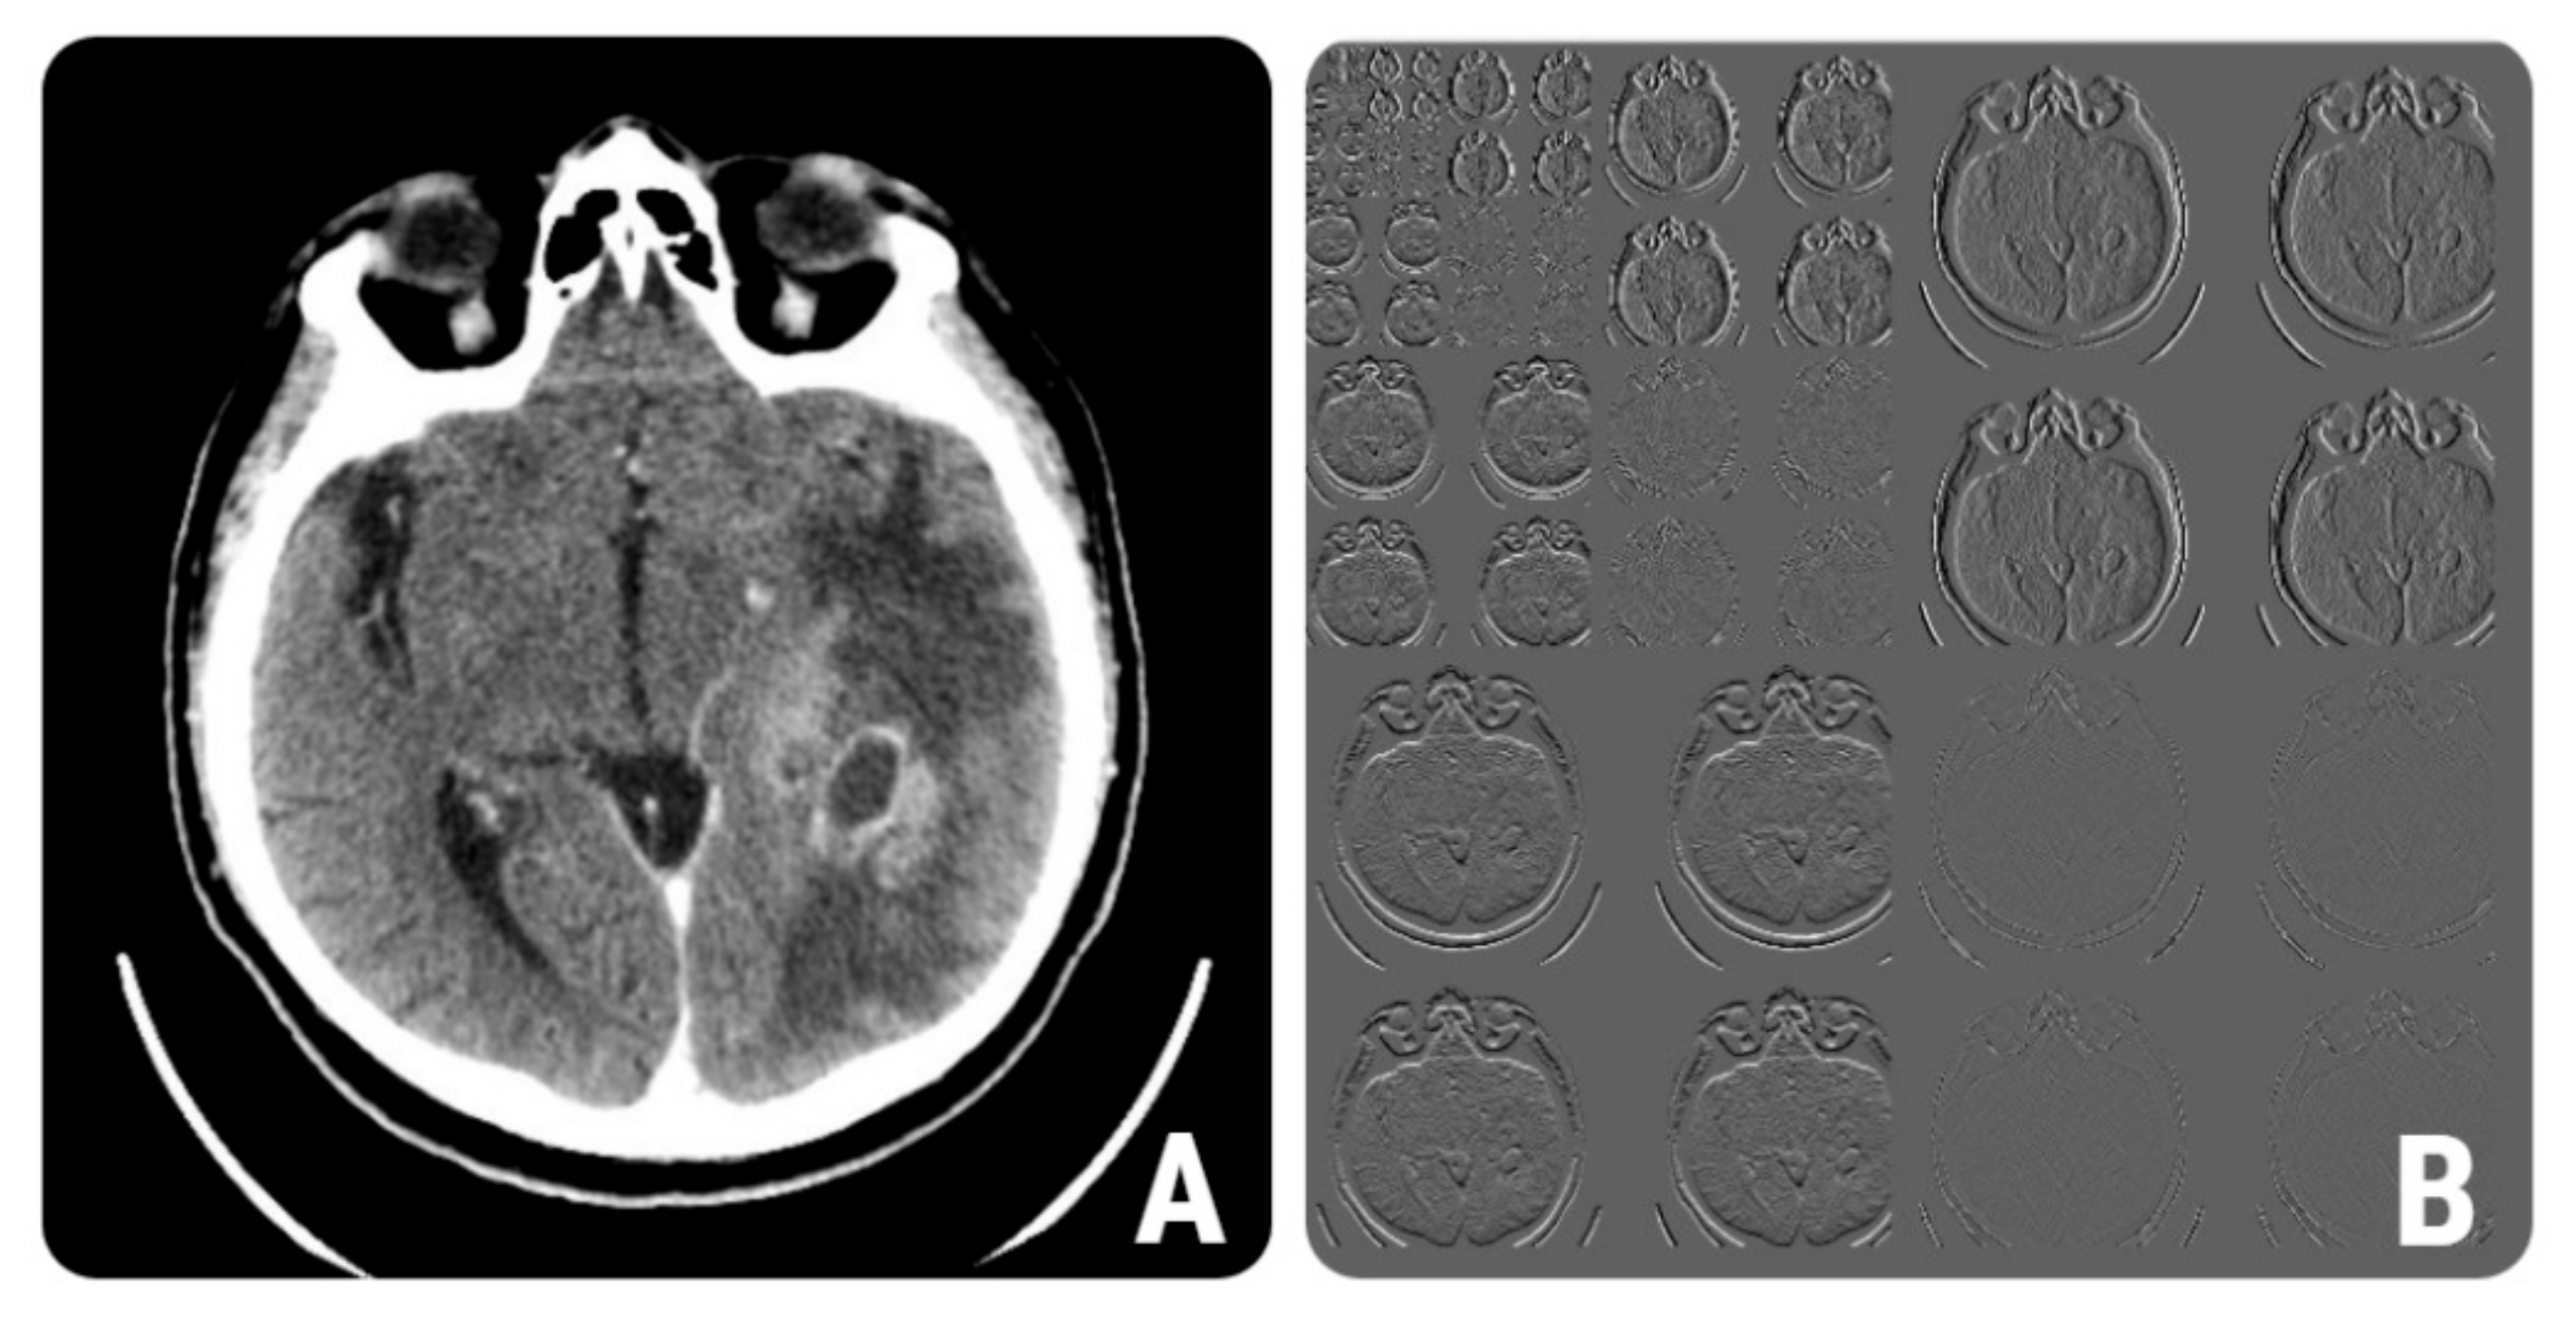

2.4.1. Image Pre-Processing and Segmentation